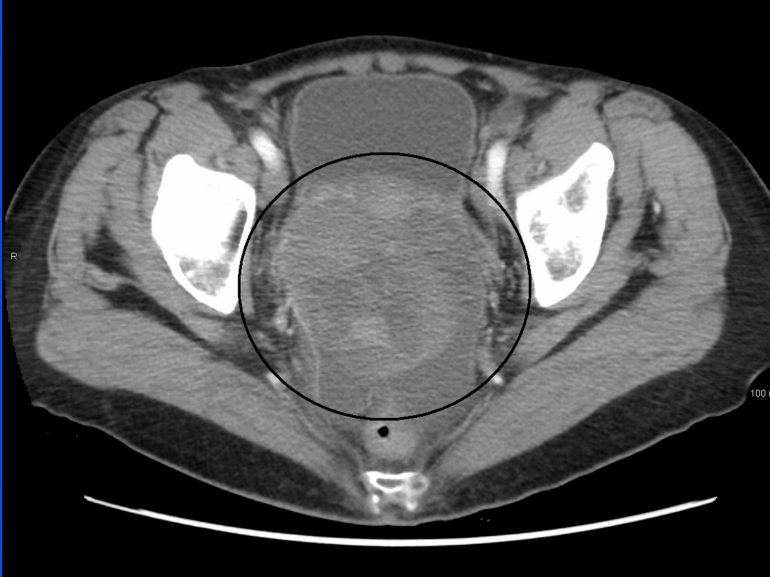

Ct Scan Cancer Risk Calculator

Ct Scan Cancer Risk Calculator. Stamina cardio exercise bike assembly video; These statistics are averages and do not predict what is going to happen to you.

Ct Scan Risk Calculator ct scan machine

Ct Scan Risk Calculator ct scan machine from ctscanmachines.blogspot.com

An mri scan does not have harmful ionizing. How to prepare for a ct scan. Based on the harvard cancer risk index developed by the harvard center for cancer prevention.